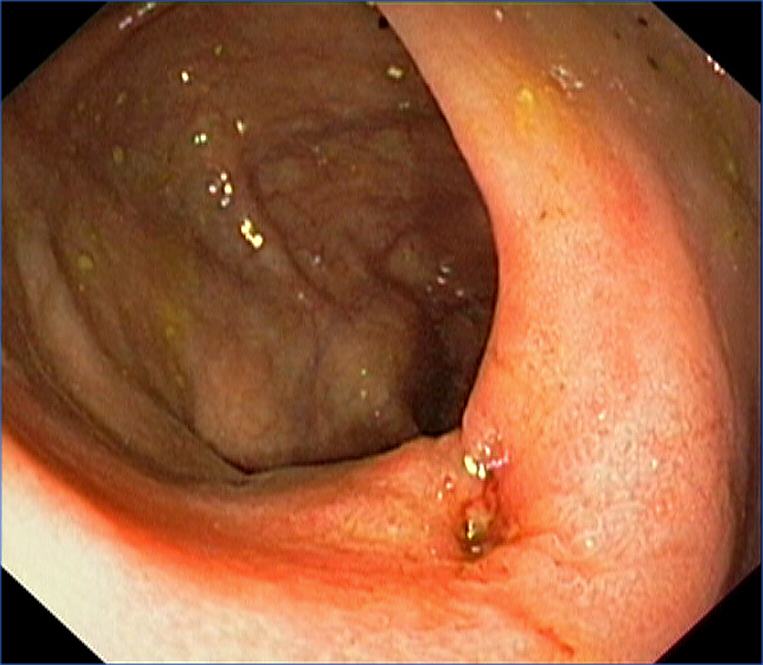

Ileocaecal valve